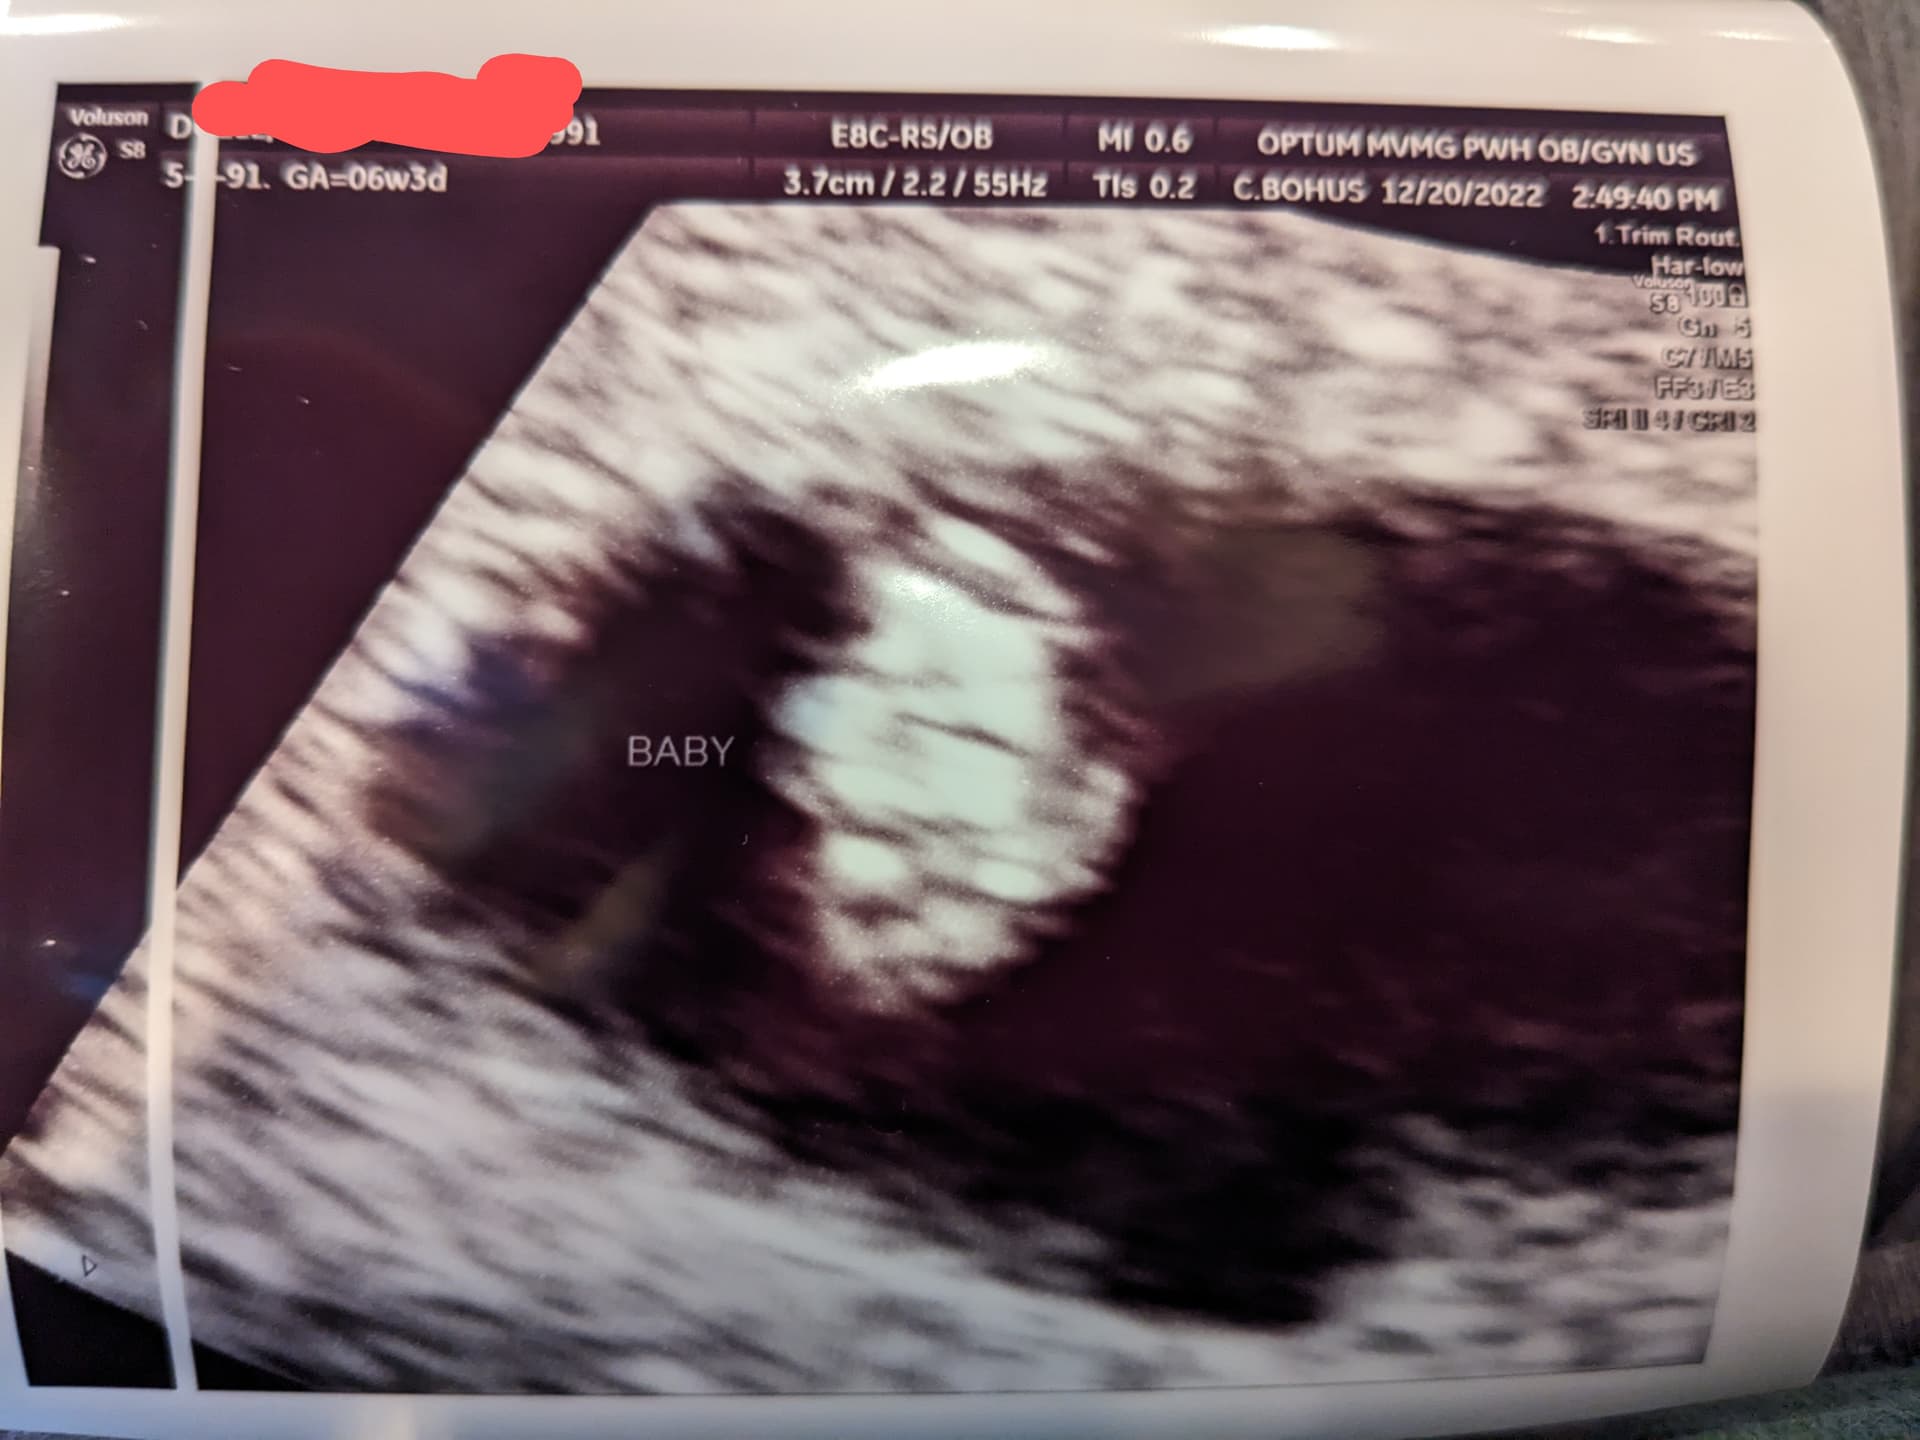

Little update

Good

Measuring 6w4d (just a day under my guess, which is within range)

HR 122 bpm

Is a blob

Doc is happy with those #s.